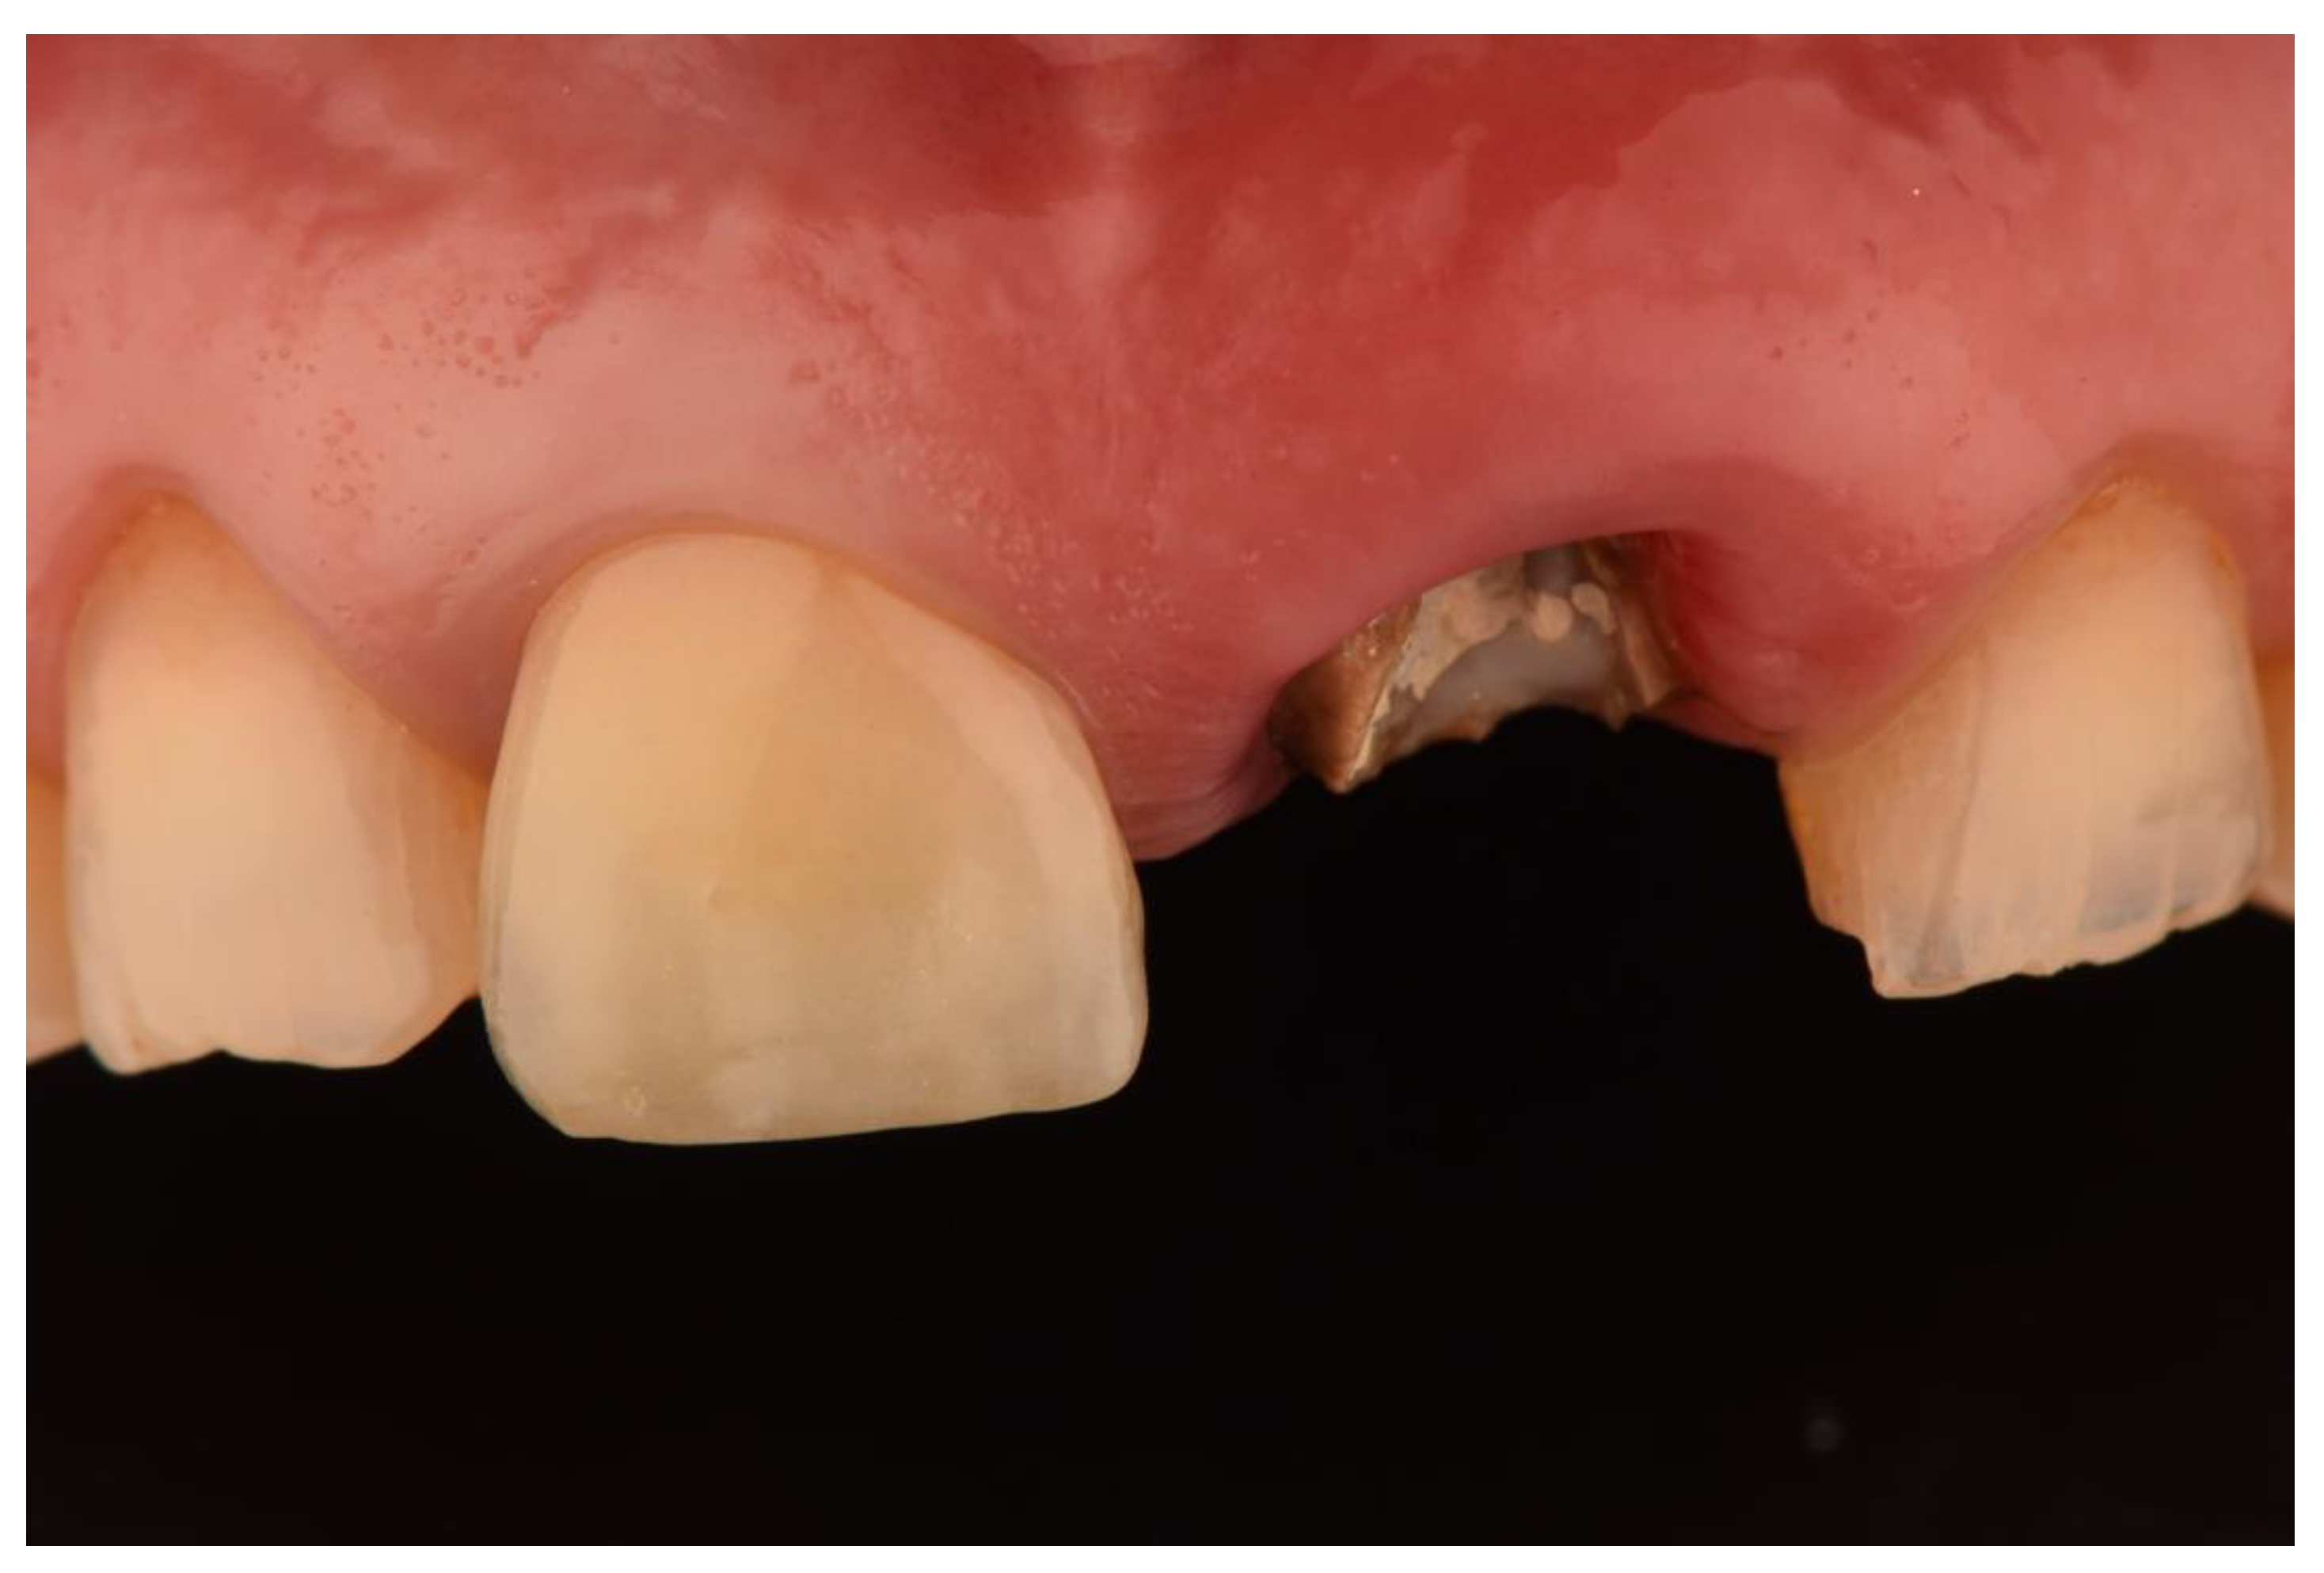

- Vilor-Fernández, V.; García-de-la-Fuente, A.M.; Marichalar-Mendia, X.; Estefanía-Fresco, R.; Aguirre-Zorzano, L.A. Single tooth restoration in the maxillary esthetic zone using a one-piece ceramic implant with 1 year of follow-up: Case series. Int. J. Implant. Dent. 2021, 7, 26. [Google Scholar] [CrossRef] [PubMed]